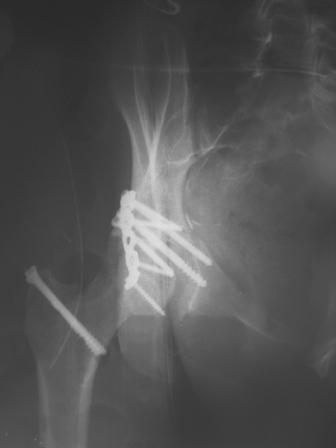

30/11/04 |  30/11/04 |  30/11/04 |  14/12/04 |  14/12/04 |  14/02/05 |  14/02/05 |  21/02/05 | Уважаемые коллеги! Случилось вторичное смещение вертлужной впадины после операции. Посоветуйте, что делать. Пациентка 18 лет. Травма 19.11.04. D.s.: Закрытыый Т-образный высокий перелом правой вертлужной впадины. Закрытый перелом м\мыщелкового возвышения левой б\берцовой кости. 9.12.04 операция - открытая репозиция, остеосинтез переломам вертлужной впадины. 30.12.05 выписаны на амбулаторное лечение с рекомендациями не вставать на правую ногу. 14.02.05 при контрольном осмотре на Р-граммах выявлено вторичное смещение передней колонны. Клинически подвывиха нет, имеется умеренная приводящая контрактура правого тазобедренного сустава, гипотрофия мышц н\конечностей. Госпитализирована в травмотделение. Выполнено КТ. Имеется смещение передней колонны кнутриЮ диастаз 8 мм. Посоветуйте пожалуйста, что предпринять в данной ситуации.